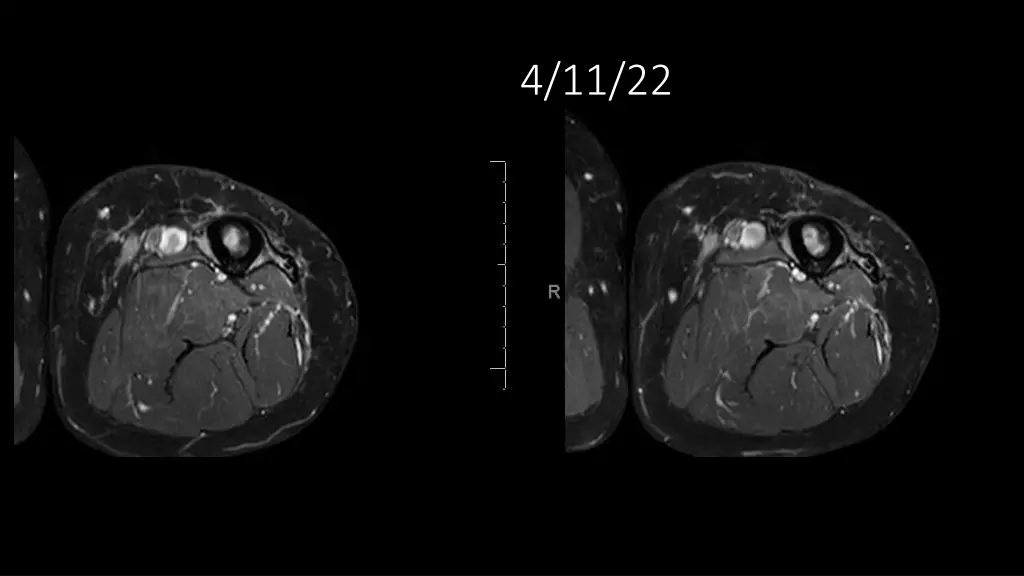

62-year-old shows post-surgery progress from 11/4/2020 to 4/11/22

Explore the journey of a 62-year-old individual post-UPS resection on 11/4/2020, through a series of dated images leading up to 4/11/22. Witness the transformation and recovery process in these visual updates reflecting the progression over time.